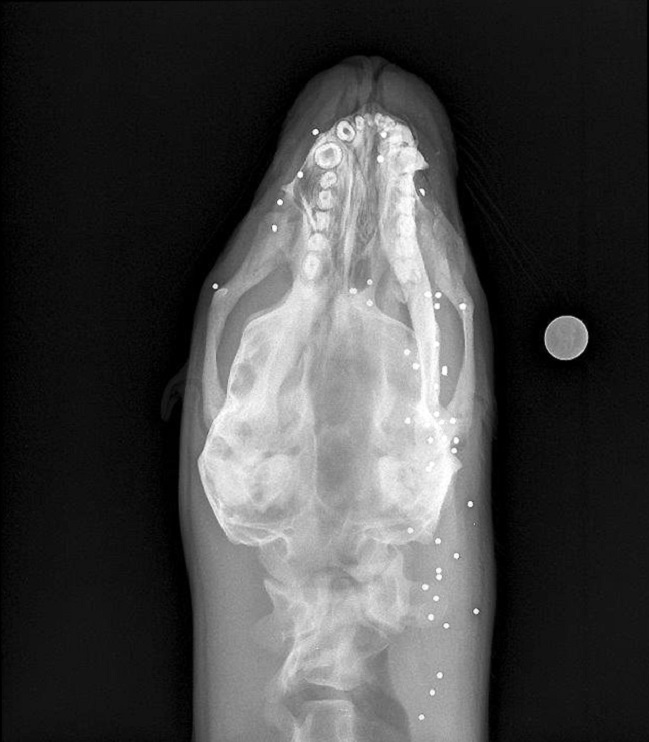

El animal había sido encontrado con múltiples lesiones en su cuerpo ocasionadas por disparos de escopeta: en total tenía 43 perdigones alojados.

"Se trató de una hembra, juvenil, que presentó múltiples perdigones en la cara, cabeza y cuello, presentando úlceras corneales en ambos globos oculares, lo que le generó ceguera", explicó la patóloga, Ana-Lía Henríquez.